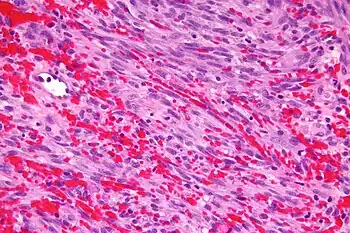

- Kaposi's sarcoma – an angioproliferative tumor that can involve skin (most often), lymph nodes, or viscera,